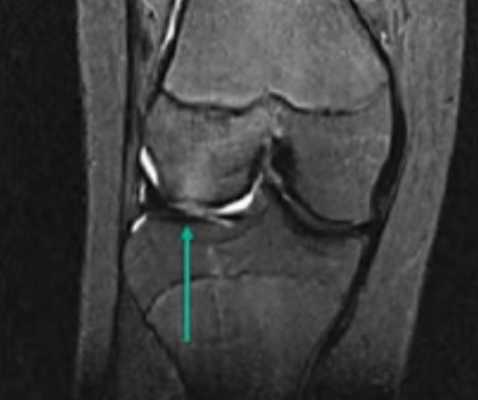

МР-изображение субхондрального перелома латерального мыщелка (зона повреждения указана стрелкой)

Протокол магнитно-резонансной томографии подытоживают заключением. В этом разделе документа интерпретируют патологические изменения, обнаруженные на срезах. Заключение МРТ коленного сустава может выглядеть так:

«На серии томограмм картина выявлена латеропозиция надколенника, повреждения медиального удерживателя и хондромаляция хряща последнего. Умеренный посттравматический отек тела Гоффа. Экссудативный синовит. Бурсит инфрапателлярной сумки. Умеренный отек мягких тканей в подколенной области».

В заключении МРТ обозначают суть и распространенность патологических процессов. При выдаче результатов рентгенолог может кратко пояснить медицинские термины и порекомендовать пациенту, к какому врачу обратиться.